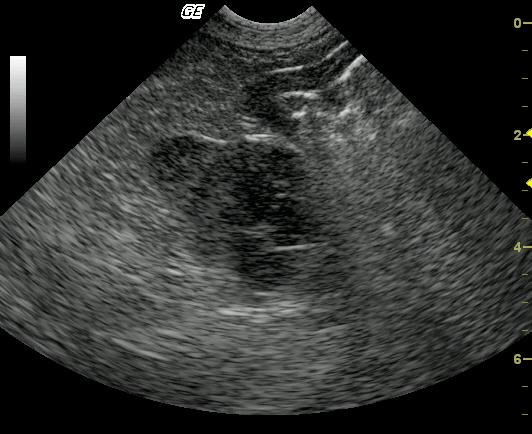

This 10 year old neutered male Beagle cross was presented for altered behavior. The physical exam was normal. CBC was normal while the blood chemistry revealed moderately elevated SAP and a slightly elevated total protein and slightly elevated globulin. The urinalysis revealed USG of 1.021 and 4+ proteinuria with inactive sediment. ACTH stimulation test was normal.